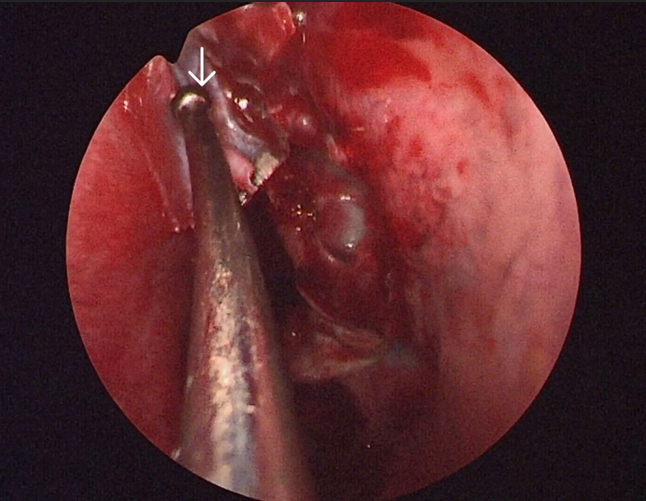

The surgery was performed under general anaesthesia by the first author. Nasal endoscopic examination after administering general anaesthesia showed watery discharge from the region of the left cribriform plate (figure3 B) and the left spheno-ethmoidal recess (figure 4). The surgery proceeded with left partial middle turbinectomy and widening of the sphenoid ostium on the left side. This was followed by left uncinectomy, middle meatal antrostomy, left anterior ethmoidectomy an removal of basal lamella and posterior ethmoidectomy. This was followed by clear delineation of the leak in the left cribriform plate and a wide sphenoidotomy (figure 5). The edematous sphenoid sinus mucosa was removed and the meningoencephalocele was seen in the left lateral recess above the vidian-rotundum line. The sphenoplalatine foramen was identified and the sphenopalatine artery cauterized. The medial aspect of the posterior wall of left maxillary sinus was removed partially. The upper part of the pterygoid process was drilled out and widened laterally exposing the antero-medial temporal lobe and the meningoencephalocele (figure 6) and the continuous csf leak leak identified.

Figure 6. Arrow showing the meningoencephalocele in the left lateral recess of sphenoid with csf leak through the defect